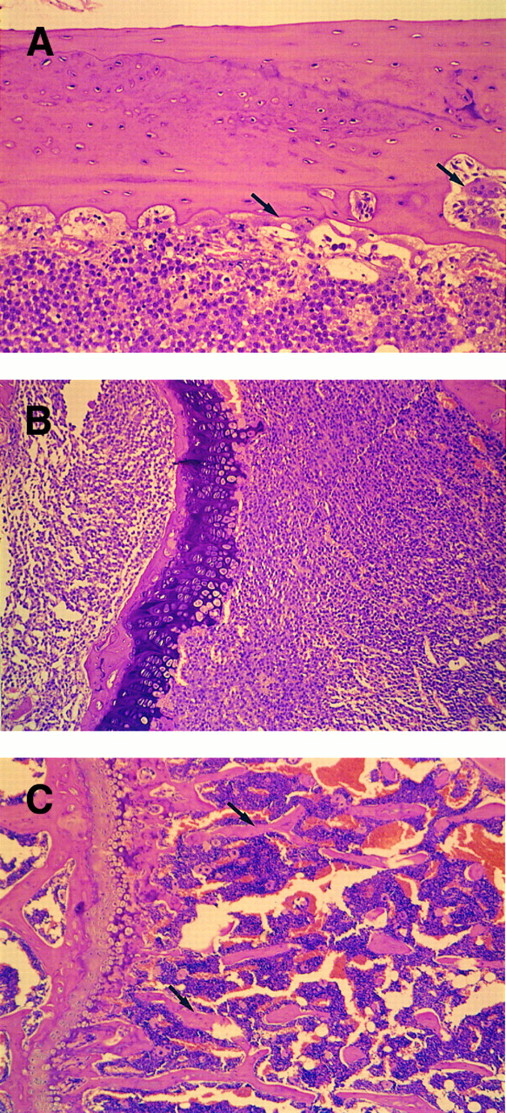

Morphologic changes of the bones were examined by the thin sections in which the bone marrow of femur was largely occupied by plasmablastic cells (Fig 4). Typical osteolytic lesions were formed in cortical bone, where polynuclear osteoclastic cells were located (Fig 4A). Moreover, spongy bone in the end of femur was completely resorbed (Fig 4B).

Histologic observation of bone resorption in the mice IV inoculated with KPMM2 cells. (A, B) Tumor-bearing mouse. (C) Normal mouse. (A) Osteolytic lesions and osteoclastic cells (arrow) were observed in cortical bone surface. Bone marrow was occupied by tumor cells. (B) The end of femur. Spongy bone completely disappeared in IV transplanted mouse. (C) Spongy bone (arrow) was observed in normal mouse.